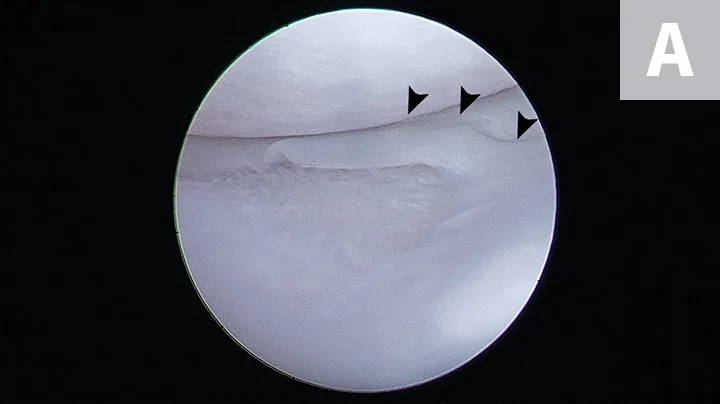

FIGURE 3

Intraoperative image demonstrating identification of medial meniscal tears by craniomedial arthrotomy in the dog in Figure 2. A Hohmann retractor (H) has been placed to allow inspection of the caudal joint space. The caudal pole of the medial meniscus has sustained a bucket handle tear and is flipped cranially (arrow).